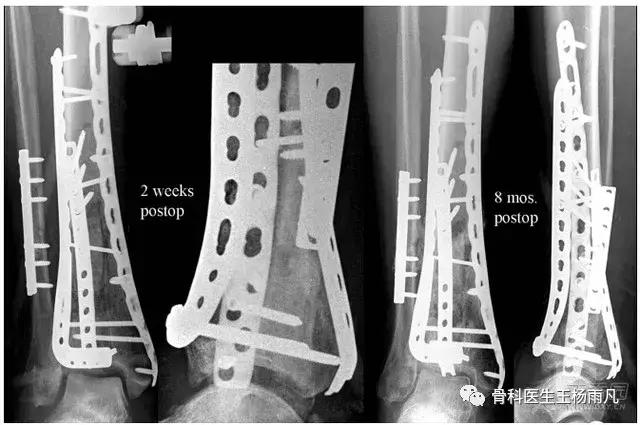

3在体内放置时间过久的钢板

钢板在体内放置时间越长,金属钢板和螺钉之间越容易出现问题,加上周围骨痂骨痂已经牢固包绕钢板生长,再加上十几年前上钢板所用的配套器械早已更新换代,这种钢板取起来特别容易出现滑丝、断钉和取钉困难的情况。除非逼不得已,否则不要取。